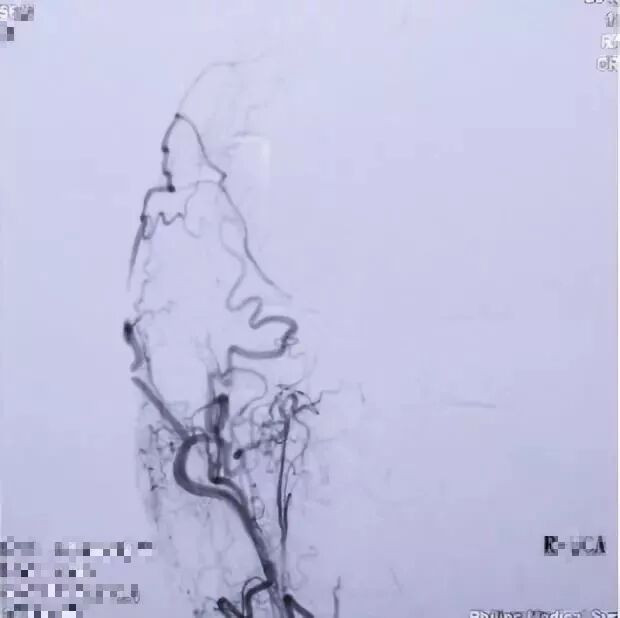

2017.04 DSA R-ICA

2017.04 DSA L-ICA